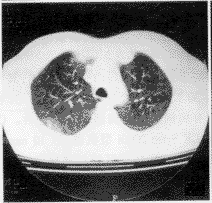

2.全身表現 常表現有上呼吸道症狀,如咳嗽、咯血或肺部空洞形成;血管炎症表現為慢性動脈炎、急性動脈炎、小動脈炎和毛細血管炎;皮膚出現皮疹、出血或壞死;胃腸道發生血管炎而出血;體重下降,全身不適和發熱較常見,部分患者可死於壞死性腎小球性腎炎。

Wegner肉芽腫的組織學改變主要有3種:實質性組織損傷、血管炎和肉芽腫性炎症。部分檢查還必須實施某些特殊染色以排除是否有微生物存在。炎症性浸潤是由不同比例的中性粒細胞、淋巴細胞、漿細胞、組織細胞和嗜酸性粒細胞混合而成。炎症反應有在特定部位造成總效應的趨勢, 如縱隔、後腹膜和眼眶,可刺激產生腫瘤樣改變。實質性組織壞死的表現可從中性粒細胞的微膿腫到局灶性大塊壞死。血管炎可表現為數種形式 包括慢性動脈炎、急性動脈炎、小動脈炎、毛細血管炎和小靜脈炎。這些形式經常互相交織。偶爾也可觀察到肉芽腫性血管炎。通常可觀察到血管壁壞死,帶有變性的白細胞碎片,但觀察不到類纖維樣壞死。